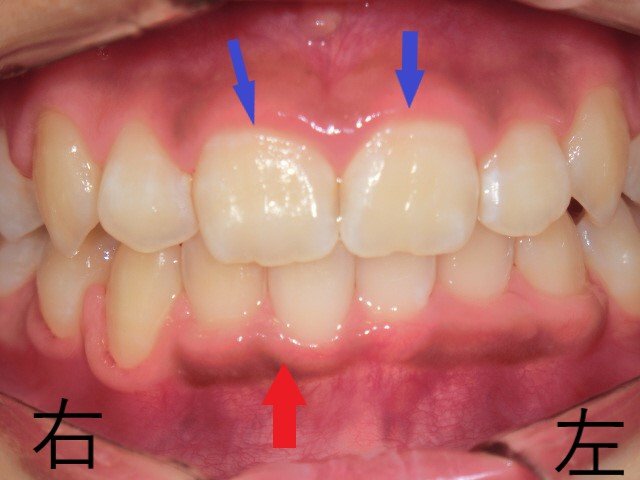

さらに6か月後(12歳時)には、第一大臼歯までの永久歯がすべて萌出し、左右の上顎犬歯も正常に並んだことを確認できたため、一次治療は終了としました。

・ 12歳時:上顎の拡大がさらに進行し、左上犬歯が正常な位置に萌出し、歯列に収まりました